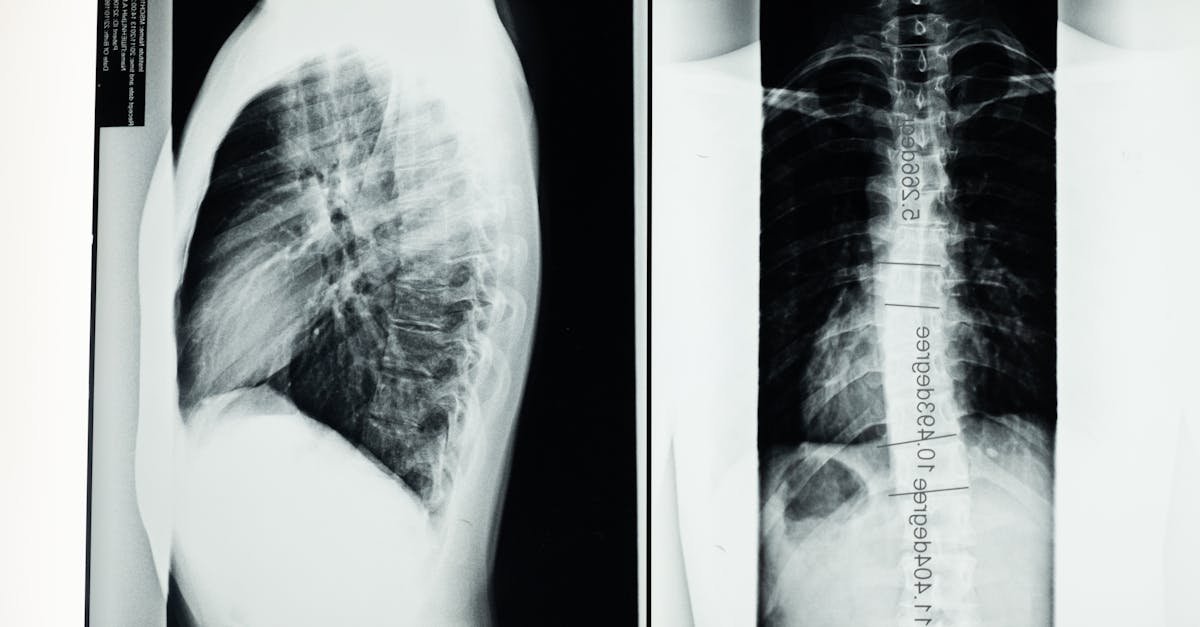

Les examens d’imagerie, notamment l’IRM, jouent un rôle clé dans le diagnostic. L’IRM permet de visualiser la colonne vertébrale et d’identifier des anomalies telles que le bombement discal. Une IRM dynamique peut également être utilisée pour observer le comportement de la colonne lors des mouvements, ce qui aide à détecter des compressions nerveuses que l’IRM standard pourrait ne pas montrer.

La prochaine étape cruciale est la réalisation d’examens d’imagerie médicale. L’IRM est généralement l’examen privilégié, car il permet de visualiser les tissus mous et d’identifier les bombements discaux. En effet, l’IRM fournit des images détaillées qui permettent de visualiser l’emplacement et la gravité du bombement, ainsi que l’impact sur les nerfs voisins.

D’autres techniques d’imagerie, comme la ciné-IRM, peuvent également être pertinentes. Cet examen dynamique permet d’observer la colonne vertébrale en mouvement, ce qui peut révéler des caractéristiques du bombement non visibles dans une IRM standard. L’analyse des images obtenues aide à déterminer le degré de la compression nerveuse et l’impact fonctionnel de la condition sur le patient.

Une fois l’évaluation physique réalisée, le médecin peut recommander des examens d’imagerie médicale. L’IRM est souvent la méthode privilégiée, car elle permet de visualiser les tissus mous, les nerfs et les caractéristiques du disque intervertébral. C’est un outil précieux pour détecter le bombement discal ainsi que la sténose associée. Pour obtenir des informations plus détaillées, une IRM dynamique, qui évalue la colonne vertébrale en mouvement, peut aussi être prescrite. Cet examen permet d’observer les changements structurels et fonctionnels du disque sous différentes positions et niveaux de flexion.

Les examens d’imagerie médicale représentent la pierre angulaire du diagnostic. Ils permettent de visualiser la structure des disques intervertébraux et d’identifier la gravité de la sténose associée. Les techniques comme la ciné-IRM apportent des informations cruciales, car elles révèlent comment le bombement discal influence le canal rachidien lors des mouvements, offrant ainsi une vision plus dynamique de la condition du patient.